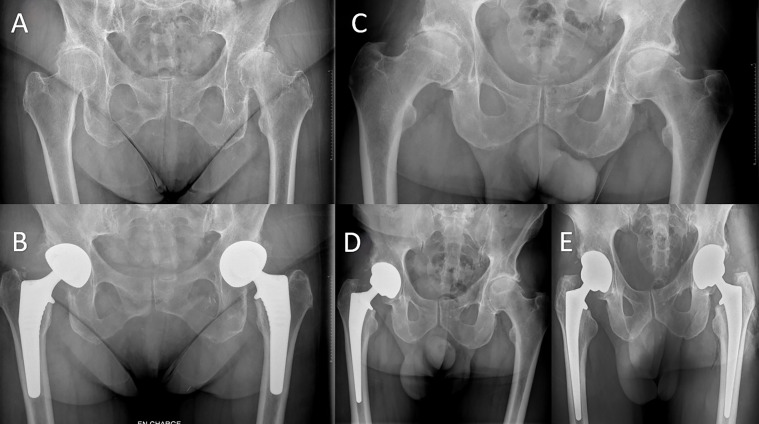

简介:同步双侧全髋关节置换术(THA)的临床效果与分期双侧THA相似。然而,有关术后早期并发症的数据却很少。本研究比较了同时双侧全髋关节置换术和直接前路(DAA)分期双侧全髋关节置换术在早期并发症和翻修手术方面的情况:这项回顾性病例对照研究纳入了2013年至2021年间所有采用DAA进行的双侧THA,随访时间至少6个月。共确定了 264 例 THAs(132 例患者)[同期组(1T):58 例患者;分期组(2T):74 例],平均随访 54 个月。在最后一次随访时对并发症和翻修、临床疗效和停工天数进行了评估。此外,还采用 Mercuriali 和 Inghilleri 的改良方法对失血量进行了评估:结果:1T 组的失血量更高(1T 组为 1003 毫升,2T 组为 740 毫升;P 讨论):使用 DAA 同时进行双侧 THA 似乎是一种安全的手术,与分期手术相比,术后早期并发症增加的风险不大,功能结果相似,并发症和停工天数明显减少。

Introduction: Simultaneous bilateral total hip arthroplasty (THA) has demonstrated similar clinical outcomes to staged bilateral THA. However, there is scarce data regarding the early postoperative complications. This study compares simultaneous to staged bilateral THA with the direct anterior approach (DAA) regarding early complications and revision surgeries.

Methods: This retrospective case-control study included all bilateral THAs, performed by DAA between 2013 and 2021 with a minimum follow-up of 6 months. A total of 264 THAs (132 patients) were identified [simultaneous group (1T): 58 patients; staged group (2T): 74] with a mean follow-up of 54 months. Complications and revisions, clinical outcomes, and days off work were assessed at the last follow-up. Moreover, blood loss was evaluated by the modified method of Mercuriali and Inghilleri.

Results: Blood loss was higher in the 1T group (1003 mL 1T vs. 740 mL 2T; p < 0.001) but there was no significant difference in transfusion rates (5% 1T vs. 3% 2T; p = 0.4). There were no complications in 1T, while the complication rate was 5.2% (n = 6) in 2T (p = 0.012). There were 5 revisions in the 2T group, including 2 debridements with polyethylene exchange and implant retention for early infections, 2 revisions for aseptic loosening in the same patient, and 1 revision due to fracture. Postoperative pain on D3 was equivalent in both groups (4.2 1T vs. 4.3 2T; p = 0.79). The improvement in function according to the HHS at 2 months was better in the 1T group, but not significant (36.8 1T vs. 32.9 2T; p = 0.05). The total number of days off work was significantly higher in the 2T group (82.6 days vs. 178.8; p = 0.025).

Discussion: Simultaneous bilateral THA with the DAA seems to be a safe procedure, with no risk of increased early postoperative complications when compared to the staged procedure with similar functional outcomes and significantly fewer complications and days off work.